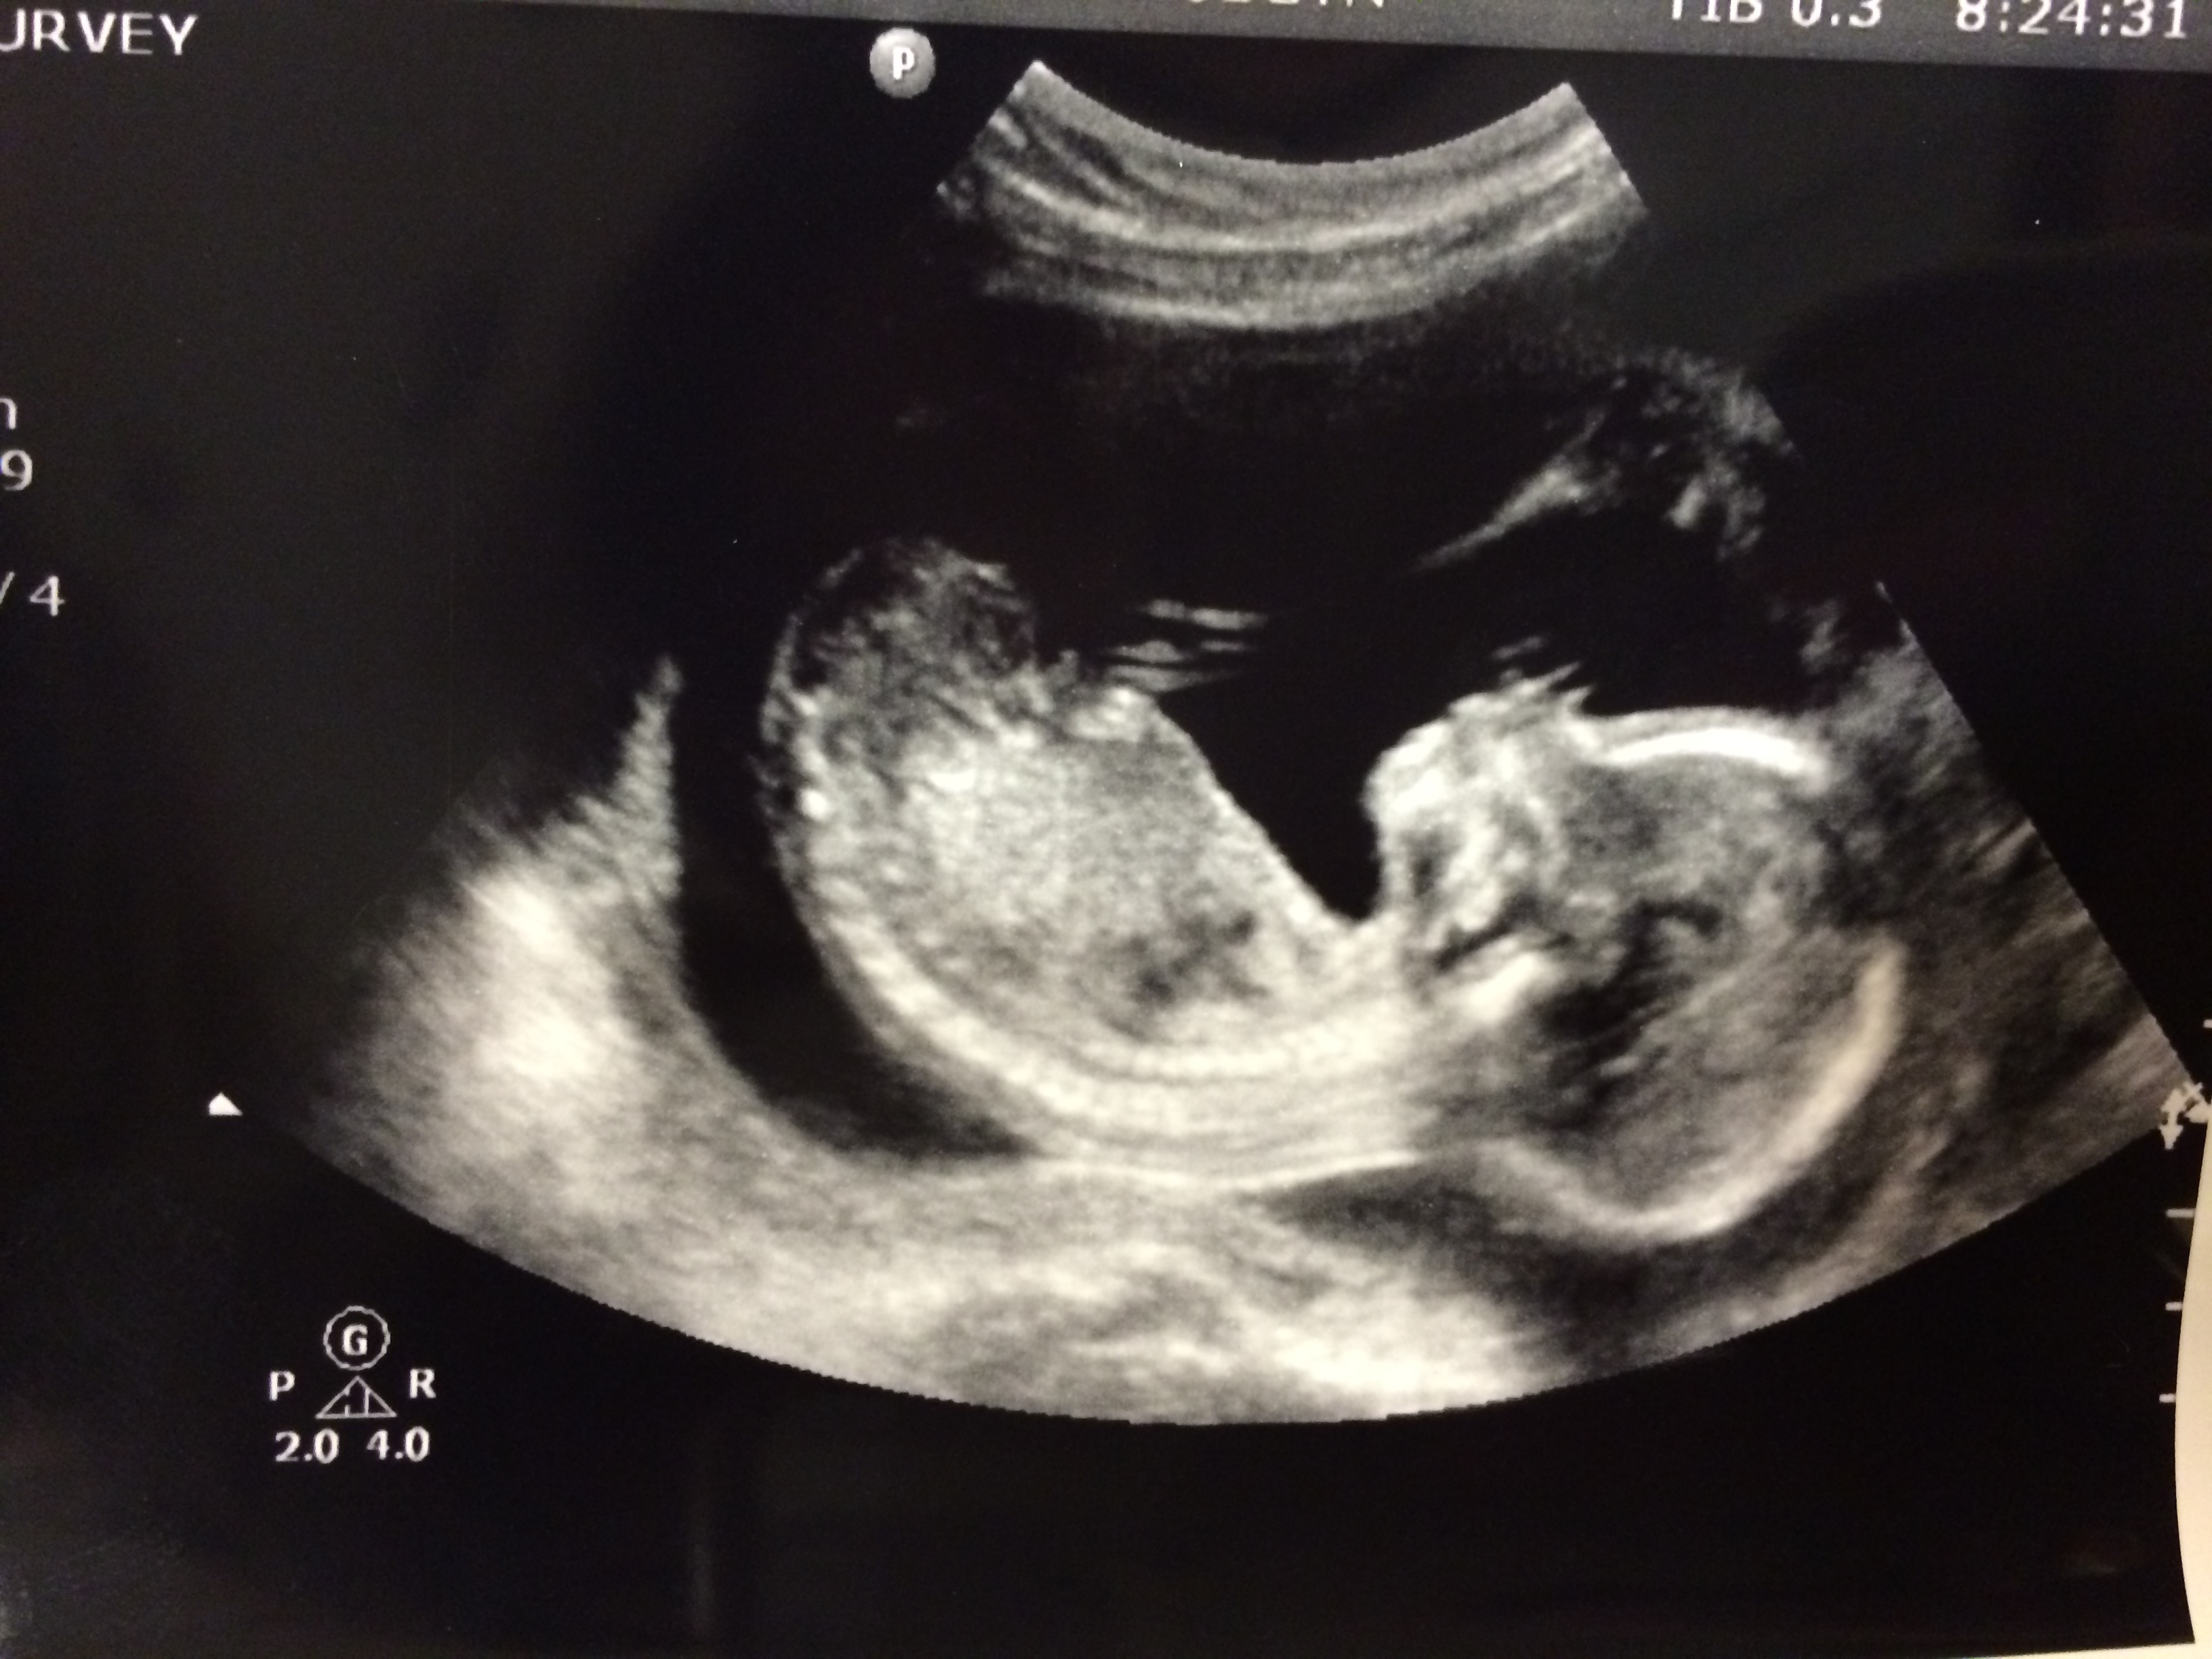

I am 16w 6d today! We had our 16 week appointment last week and it went very well. I talked to my OB about my anxiety and she helped me feel more normal about it. We also had my first cervical check and mine was measuring at 52mm! I had a cervical surgery a couple of years ago, so my OB was concerned with it being too short. Hopefully, it stays nice and long! I have another check at 20 weeks during our a/s scan. We also got another u/s of the baby during our appointment. He/She is quite the mover! I could watch this little sweetie all day long! Our a/s is Aug 7th, so I'll have to wait until then I suppose.